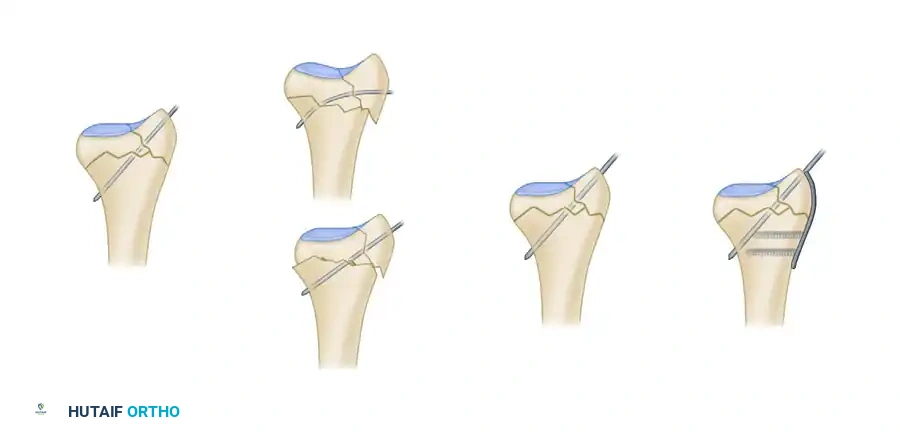

Biomechanics of Pin-Plate Fixation

Traditional radial styloid Kirschner wire fixation provides only a single point of constraint. This single point of fixation acts as a pivot, failing to prevent settling, bending, or radial drift of the distal fragments under physiological loads.

By adding a small buttress plate to the radial styloid pin, the construct is transformed. The pin-plate provides two distinct fixation points: the first through the distal end of the plate, and the second through the intact medial radial cortex. This dual-point constraint prevents collapse, resists dorsal torque, and halts radial migration.

Fragment-Specific Implants and Application

1. The Radial Pin-Plate:

Applied to the radial column, this implant enhances stability by providing a radial buttress. It effectively neutralizes bending forces that would otherwise cause the radial styloid to displace proximally and radially.

2. The Ulnar Pin-Plate:

The dorsal ulnar fragment (often involving the sigmoid notch) is stabilized with an ulnar pin-plate. By proper contouring, this plate can close gaps in the sagittal plane,